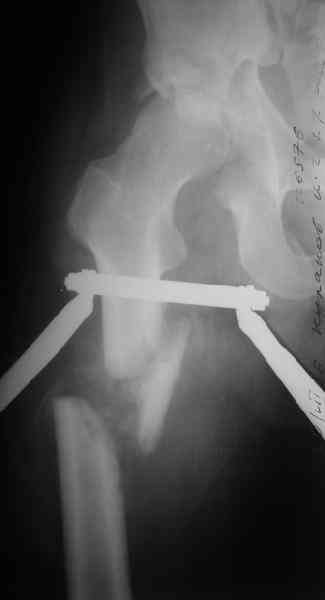

Уважаемы коллеги! Поступил непростой больной 24 лет через 1 месяц после травмы (фото в приложении). Кроме перелома правой вертлужной впадины, перелома и вывиха этого же бедра имеются переломы диафиза правой плечевой кости, диафиза правой локтевой кости, диафизов обеих костей левого предплечья.

Неврологии со стороны нижних конечностей нет. Планируем первым этапом выполнить ЗИМО длинных трубчатых костей. Вопросы: 1. имеет ли смысл в эти сроки идти на остеосинтез вертлужной впадины и вправление вывиха или планировать первичное эндопротезирование? 2. Есть у кого-нибудь ссылки или другая информация по поводу исходов лечения переломов вертлужной впадины, сопровождающихся вывихом головки бедра в разные сроки (буду очень признателен, если поделитесь)?A male 24 y.o, admitted to our unit today 1 month post injury - images attached. Except ipsilateral acetabular fx, femoral shaft fx and hip dislocation also he has shaft fxs of right humerus and ulna, left radius and ulna. No neurological deficits after the hip dislocation. At first we plan closed nailing of all long bones. Questions are regarding the acetabular fx + dislocation. With the 1 month of exposition and obvious callus everywhere does it make sense to attempt ORIF of the acetabulum with hip reduction, or primary THA should be considered? Does anybody have references on outcomes after delayed surgeries for acetabular fx + hip dislocation depending on duration of the delay? С уважением Максим Агалаков, УНИИТО Е-бург.

Now, to my own opinion. I believe that this is a Transverse + Posterior wall fracture type.

The transverse element does not seem so much displaced, and now after 1 month I believe it will be extremely difficult to mobilize and reduce. So I suggest you get a CT to check for incarcerated fragments, a high possibility in this unreduced dislocation. Then you open posteriorly, Kocher Langenbeck, with the patient prone, extract any incarcerated frgments, reduce the hip, fix the posterior wall by screws, and then apply a contoured reconstruction plate from the iliac wing to the ischium. This plate will hold the ransverse element, as well as buttress the posterior wall fragment(s).